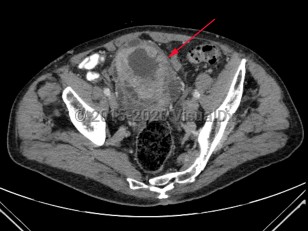

Bladder cancer

Patients with bladder cancer typically present with painless gross or microscopic hematuria, although dysuria, frequency, and urgency may be the presenting symptoms. Diagnosis may be delayed due to the similarity of these symptoms to benign conditions such as urinary tract infections, nephrolithiasis, cystitis, or prostatitis. Urothelial cancer may mimic bladder cancer. In patients younger than 50 years, asymptomatic microscopic hematuria is rarely associated with bladder cancer.

Treatment options depend on depth of tumor invasion and presence or absence of metastatic disease. Transurethral resection of bladder tumor (TURBT) may be combined with adjuvant chemotherapy for early-stage disease with radical cystectomy and/or chemotherapy in late-stage disease.